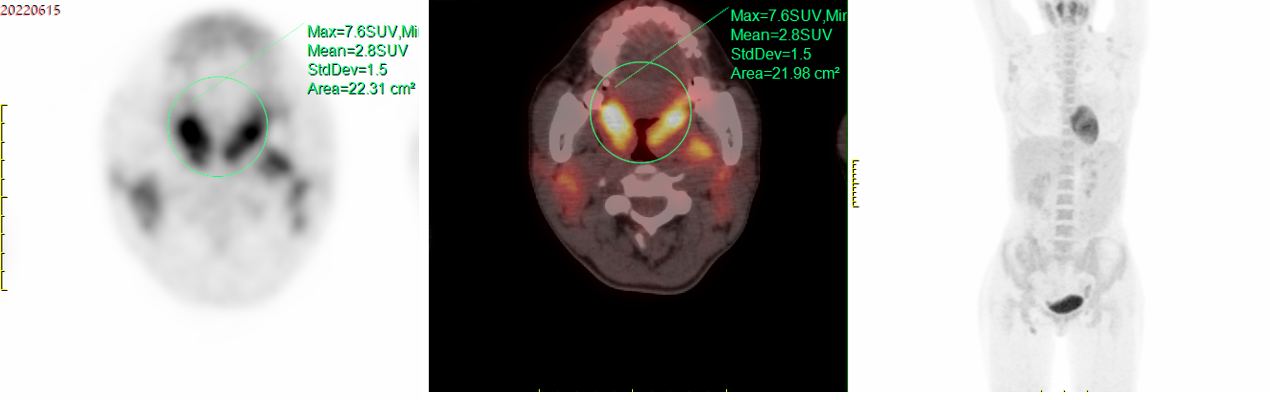

PET-CT(2022-06-15):鼻咽部、两侧扁桃体软组织增厚,FDG代谢对称性增高(SUVmax 7.6);两侧颈部、两侧腋窝、两侧髂内、腹股沟区多发增大淋巴结,较大约2.8cm×1.5cm,FDG代谢增高(SUVmax 5.1);脾大,FDG代谢未见异常增高;全身骨髓FDG代谢弥漫性轻度增高;结合病史,符合CLL表现,目前尚无Richter转化征象。2、右侧上颌窦炎。3、右肺下叶慢性炎症。

2022-06-15 PET-CT